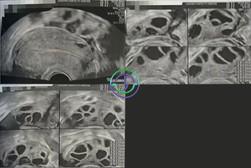

促排第 10 天 — 多个卵泡已长大,但部分尚未成熟;继续用药

超声结果

右侧卵巢:卵泡大小 18,18,18,17,17,14,14,14,13,13,12 mm → 共 11 个卵泡

左侧卵巢:卵泡大小 20,19,19,18,18,17,17,17,17,16,16 mm → 共 11 个卵泡